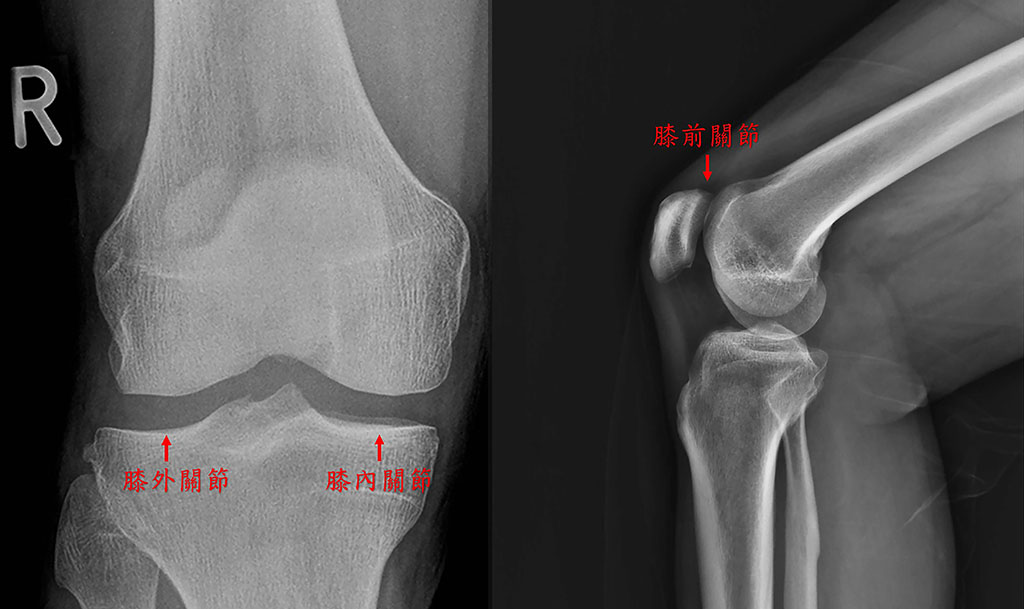

收治病例的彰基醫學中心骨科部主治醫師陳志鎧表示,膝關節由股骨、脛骨及髕骨所構成,總共可以分成三個小關節 - 內、外、前關節;而之間有半月板、關節液與韌帶,維持整個關節的飽滿與穩定。因為年齡、疾病、或是創傷,造成半月板或是軟骨的受傷,進而關節液的減少,引發一連串發炎物質開始破壞關節腔。早期的症狀除了紅熱腫痛之外,還容易發炎積水,更嚴重的是,常常會靠著另外一側相對健康的膝蓋跛行,因而兩側膝蓋輪流疼痛,最後兩側膝蓋都同步退化。

正常膝關節分成膝外關節(左)、膝內關節(中)及膝前關節(右),三個部份。